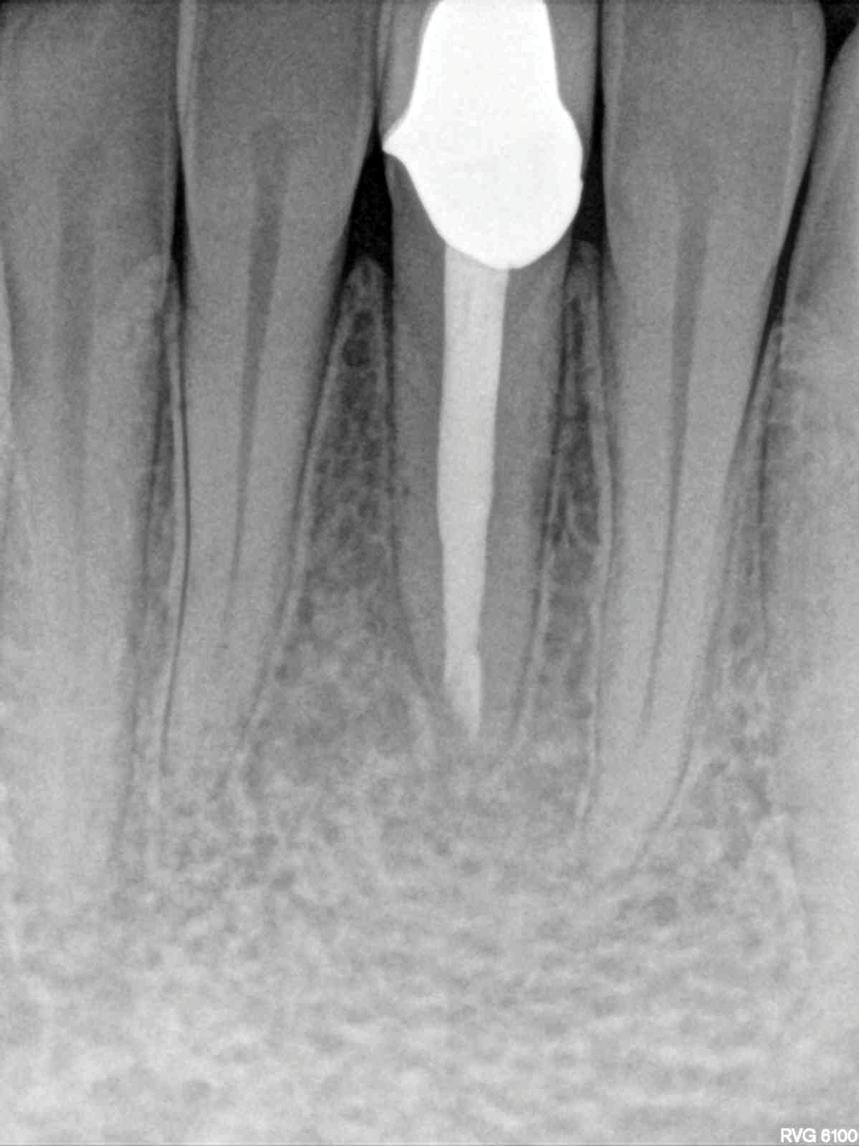

Fig 1 through Fig 5. NSRCT can have high success, even with risk factors like periapical pathology associated, as depicted in this case presentation. Fig 1: Preoperative periapical radiograph showing AP. Fig 2: Preoperative CBCT. Fig 3: Immediate postoperative periapical radiograph. Fig 4: Three-month follow-up CBCT showing reduction of periapical radiolucency. Fig 5: One-year follow-up periapical radiograph showing resolution of periapical radiolucency.

Figure 3